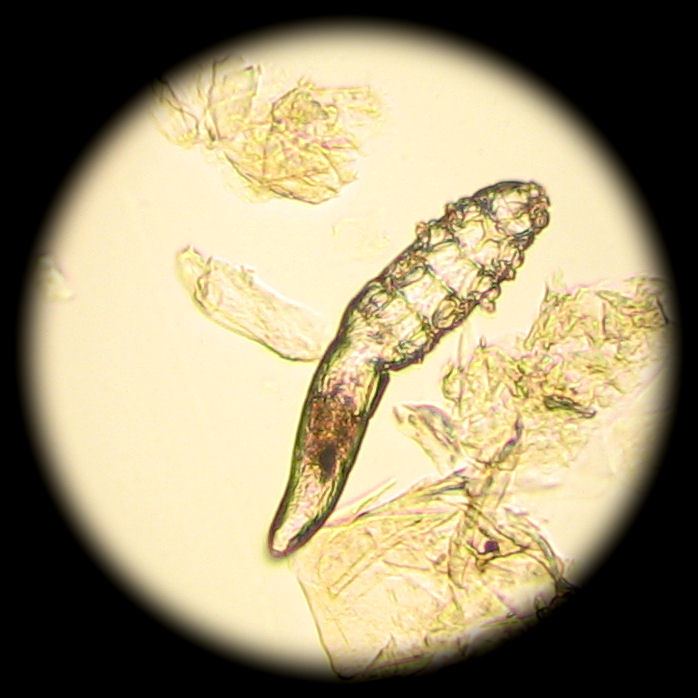

Так, например, выяснилось, что взрослый клещ достигает максимального размера до 0,4 мм. У него полупрозрачное вытянутое туловище и 8 лапок. Тело покрыто мелкими чешуйками, которые позволяют им цепляться за волосяной фолликул. Кроме того, у этого существа есть ротовой аппарат, с помощью которого ему удается поедать скапливающиеся в волосяных сумках частички сальных желез, клетки кожи и гормоны.

Анализ на клеща демодекс делается просто и безболезненно. Специалист берет соскоб кожи лица или волосяного покрова (брови, ресницы) и отправляет его на исследование в лабораторию. Далее проводится его изучение под микроскопом. Именно так можно увидеть полупрозрачных паразитов и результаты их жизнедеятельности.

image

Виновником заболевания (код по МКБ-10 — В88.0) является клещ Demodex folliculorum , продукты его жизнедеятельности. Рассмотреть врага можно лишь под микроскопом, поскольку его размеры не превышают 0,1-0,4 мм. В небольших количествах клещ встречается практически у всех людей, но редко кому доставляет неприятности – природного иммунитета, как правило, бывает достаточно, чтобы враг никак себя не обнаруживал. Однако на фоне других заболеваний и негативных обстоятельств активность клеща становится опасно высокой.